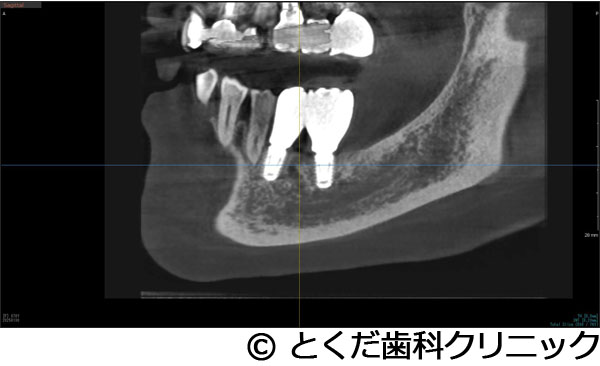

¡Ú¾ÉÎã2¡Û¤«¤Ê¤ê¾å³Ü¹ü¤¬¤Ê¤¤¡Ê¾å³Ü´û¸¹ü1.5¡Á2mm¤·¤«¤Ê¤¤¡Ë¥±¡¼¥¹¤Ç¡¢¤ï¤º¤«2¥õ·îȾ¤Ç¼£ÎŤò½ª¤¨¤¿¥±¡¼¥¹

- ¤«¤Ê¤ê¾å³Ü¹ü¤¬¤Ê¤¤¡Ê¾å³Ü´û¸¹ü1.5¡Á2mm¤·¤«¤Ê¤¤¡Ë¥±¡¼¥¹¤Ç¡¢¤ï¤º¤«2¥õ·îȾ¤Ç¼£ÎŤò½ª¤¨¤¿¥±¡¼¥¹

¼£ÎÅÊýË¡

»õ¼þɤˤè¤ê¡¢±¦Â¦6È֤ξå³Ü¹ü¤¬µÛ¼ý¤·¤Æ¡¢1.5¡Á2mmÄøÅ٤ιü¤·¤«»Ä¤Ã¤Æ¤¤¤Ê¤«¤Ã¤¿¤¿¤á¡¢½¾Íè¤Ê¤éÂ礤ʿ¯½±¤È1ǯ°Ê¾å¤Î¼£ÎÅ´ü´Ö¤¬¤«¤«¤ë¥µ¥¤¥Ê¥¹¥ê¥Õ¥È¤¬É¬ÍפǤ¢¤Ã¤¿¤¬¡¢´µ¼ÔÍͤؤλþ´ÖŪ¡¢ÆùÂÎŪ¡¢¶âÁ¬ÅªÉéô¤¬Â礤¯¤Ê¤ë¤³¤È¤ò¹Íθ¤·¤Æ¡¢º£²ó¤Ï¡¢¥¨¥¯¥¹¥È¥é¥ï¥¤¥É¥·¥ç¡¼¥È¥¤¥ó¥×¥é¥ó¥È¤È¥Ç¥ó¥µ¡¼¥Ð¡¼¤ò»ÈÍѤ·¤¿¥°¥é¥Õ¥È¥ì¥¹¥µ¥¤¥Ê¥¹¥ê¥Õ¥È¤òÁªÂò¤·¤Æ¡¢¤ï¤º¤«¡¢2.5¥õ·î¤Ç¾åÉô¥¸¥ë¥³¥Ë¥¢¤ÎºÇ½ªÊäÄÖʪ¤òÁõÃ夷¤Æ¼£ÎŤò½ª¤¨¤Æ¤¤¤Þ¤¹¡£

¹âÅ٤˵ۼý¤·¤¿¾å³Ü¹ü¤ËÂФ¹¤ë¥¤¥ó¥×¥é¥ó¥È¼£ÎŤǤ¢¤Ã¤¿¤¬¡¢¥°¥é¥Õ¥È¥ì¥¹¥µ¥¤¥Ê¥¹¥ê¥Õ¥È¤ò¹Ô¤¦¤³¤È¤Ç¡¢Ã»»þ´Ö¡Ê11½µ¡Ë¤Ç¼£ÎŤò½ª¤¨¤ë¤³¤È¤¬¤Ç¤¡¢¾å³ÜƶÆâ¤Ë°Ûʪ¤Ç¤¢¤ë¿Í¹©¹ü¤ò»ÈÍѤ·¤Æ¤¤¤Ê¤¤¤¿¤á¤Ë¡¢¥µ¥¤¥Ê¥¹¥ê¥Õ¥È¤Ç¤è¤¯µ¯¤¤ë¹çÊ»¾É¤Î¾å³Üƶ±ê¤òÈò¤±¤ë¤³¤È¤¬¤Ç¤¡¢Ã»»þ´Ö¡¢Ä㿯½±¡¢Ä㥳¥¹¥È¤Ç¼£ÎŤò½ª¤¨¤ë¤³¤È¤¬¤Ç¤¤¿¡£¾å³Ü±¦Â¦6È֤˥¤¥ó¥×¥é¥ó¥È¼£ÎŤǤ¤¿¤³¤È¤Ë¤è¤ê¡¢Òû¹ç¤¬°ÂÄê¡¢»õ¼þɤˤ괵¤·¤Æ¤¤¤ë»õ¤Ø¤ÎÉ԰¤òÍÞ¤¨¤ë¤³¤È¤¬¤Ç¤¤¿¡£